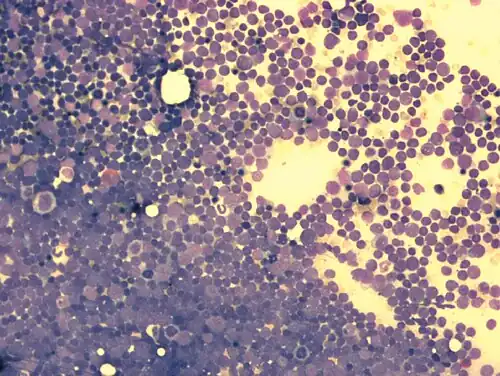

Knochenmarkausstrich bei ALL: mehr als 90 % der hier sichtbaren Zellen sind lymphatische Blasten (Leukämiezellen). Die Zelldichte ist stark gesteigert.

Knochenmarkausstrich bei ALL (Detail) mit Lymphoblasten (Leukämiezellen). Die Blasten weisen meist mehrere Nucleoli auf (Malignitätskriterium).